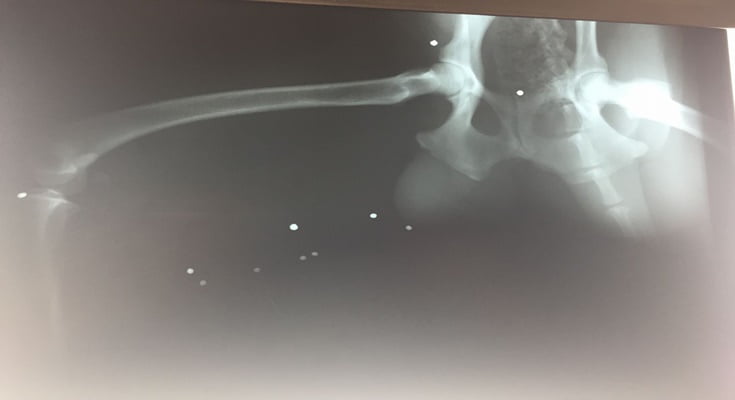

Στο σώμα του Σούτι βρέθηκαν πολλά σκάγια

Ένα μέλος μας τον φιλοξενούσε στο σπίτι του. Χτες το πρωί τον πήγαμε αμέσως στον κτηνίατρο. Πρώτα του έκανε ακτινογραφίες με απίστευτο αποτέλεσμα: Στο σώμα του Σούτι βρέθηκαν πολλά σκάγια!!!